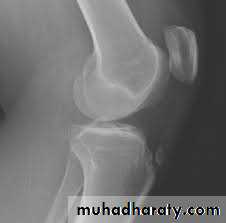

Supracondylar fractures of the femur

Typically the fracture occurs just proximally to the point where the medial and lateral cortices of the femur flare out to form condyles. In young it follow sever trauma and in old follow osteoporosis.

A vertical extension of the fracture may split the two condyles apart in a T – shaped fracture line, and sometime there is more extensive comminuation.

Clinically :

pain and deformity in lower thigh after trauma.

Knee is swollen and distal pulses should be palpated.

It may injured the popliteal artery and nerves.